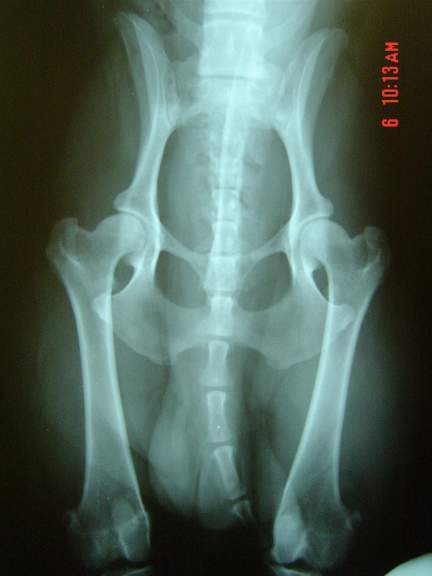

OFA Hips Good # PBG-445G54M-PI

Hip x-rays 2000

Bijou huip x-rays